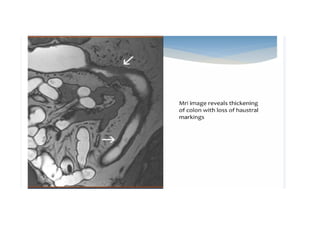

MRI/MR Enterography

• Although CECT can provide a lot of diagnostic information in

intestinal strictures; it comes with a high radiation burden

• MRI has the advantage of superior soft tissue contrast resolution;

multiplanar imaging capability and lack of any ionizing radiation.

• new ultrafast sequences (True FISP – Cine MR) have made the

real time evaluation of the small bowel possible; which is crucial

for differentiating a stricture from a peristaltic contraction.

• The active lesions tend to show restriction of diffusion

(hyperintense signal on high b value images).

• DWI can be an effective alternative to IV Gadolinium in the

evaluation of lesion activity in inflammatory bowel diseases in

patients in whom Gadolinium based contrast is contraindicated.